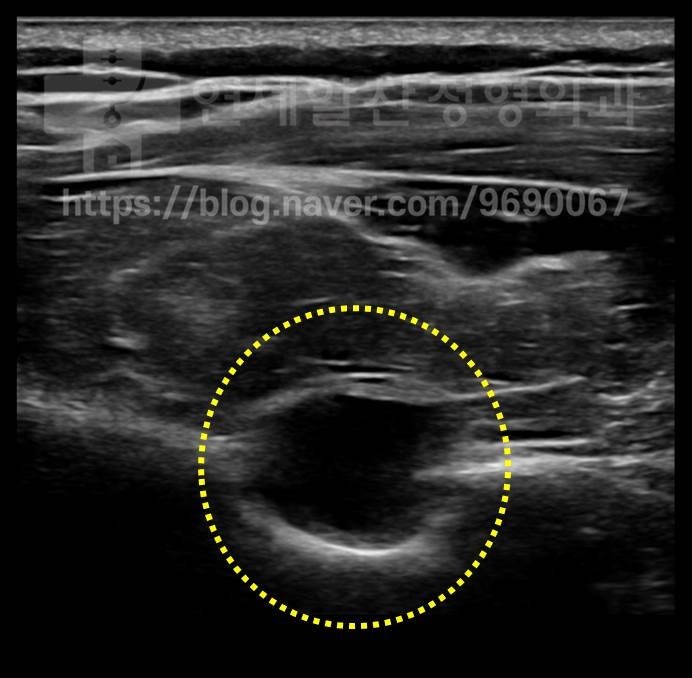

초음파상 노란색 원 안의 검은 부분이 물혹입니다.